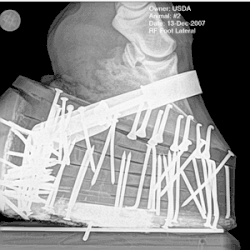

An X-ray of a horse's hoof, attached to a thick set of pads filled with nails

X-ray shows nails attaching the shoe pads that also add additional weight and could create pressure on the sole of the foot, a type of soring